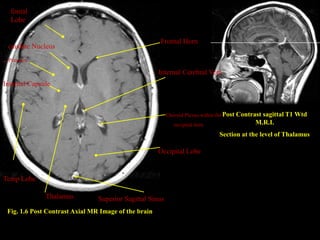

fontal

Lobe

Frontal Horn

caudate Nucleus

. Putamen

. Internal Cerebral Vein

Internal Capsule

Choroid Plexus within the Post Contrast

sagittal T1 Wtd

occipital horn                   M.R.I.

Section at the level of Thalamus

Occipital Lobe

Temp Lobe

Thalamus          Superior Sagittal Sinus

Fig. 1.6 Post Contrast Axial MR Image of the brain

fontal Lobe Frontal Horn caudate Nucleus . Putamen . Internal Cerebral Vein Internal Capsule Choroid Plexus within the Post Contrast sagittal T1 Wtd occipital horn M.R.I. Section at the level of Thalamus Occipital Lobe Temp Lobe Thalamus Superior Sagittal Sinus Fig. 1.6 Post Contrast Axial MR Image of the brain